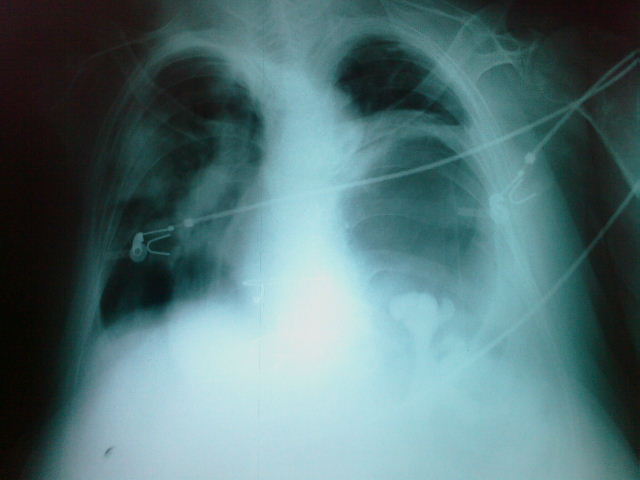

MO Distres respiratorio del adulto por trauma.